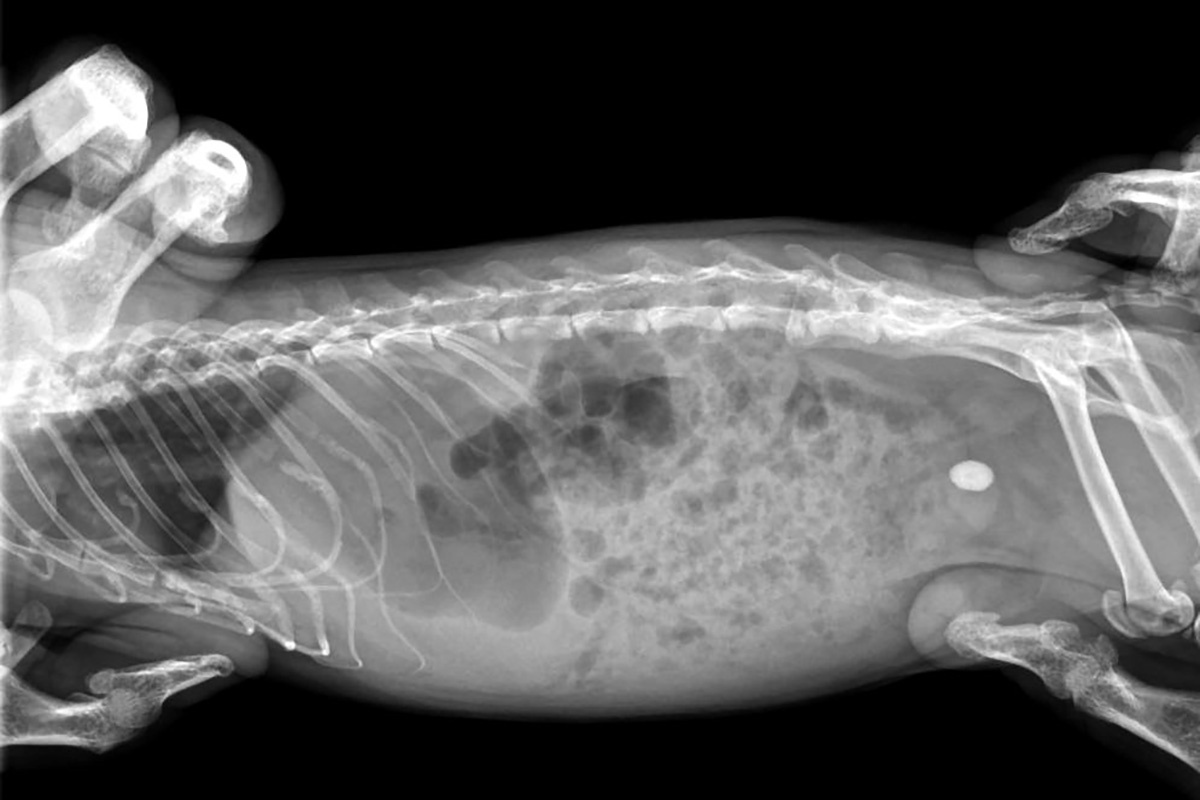

Моя Ветклиника / Telegram📷Рентген морской свинки

По ее информации, грызуну диагностировали мочекаменную болезнь, а крупный уролит (твердый биогенный минеральный конкремент в моче) грозил закупорить мочевыводящие пути. Морскую свинку доставили в Калининскую ветклинику на северо-востоке столицы, которая специализируется на хирургии грызунов и зайцеобразных.

Хирург-ратолог Сергей Маслов провел Чарли цистотомию и удалил камень из мочевого пузыря. Меньше чем через две недели питомец восстановился и хозяева привезли его в клинику, только чтобы снять послеоперационные швы.